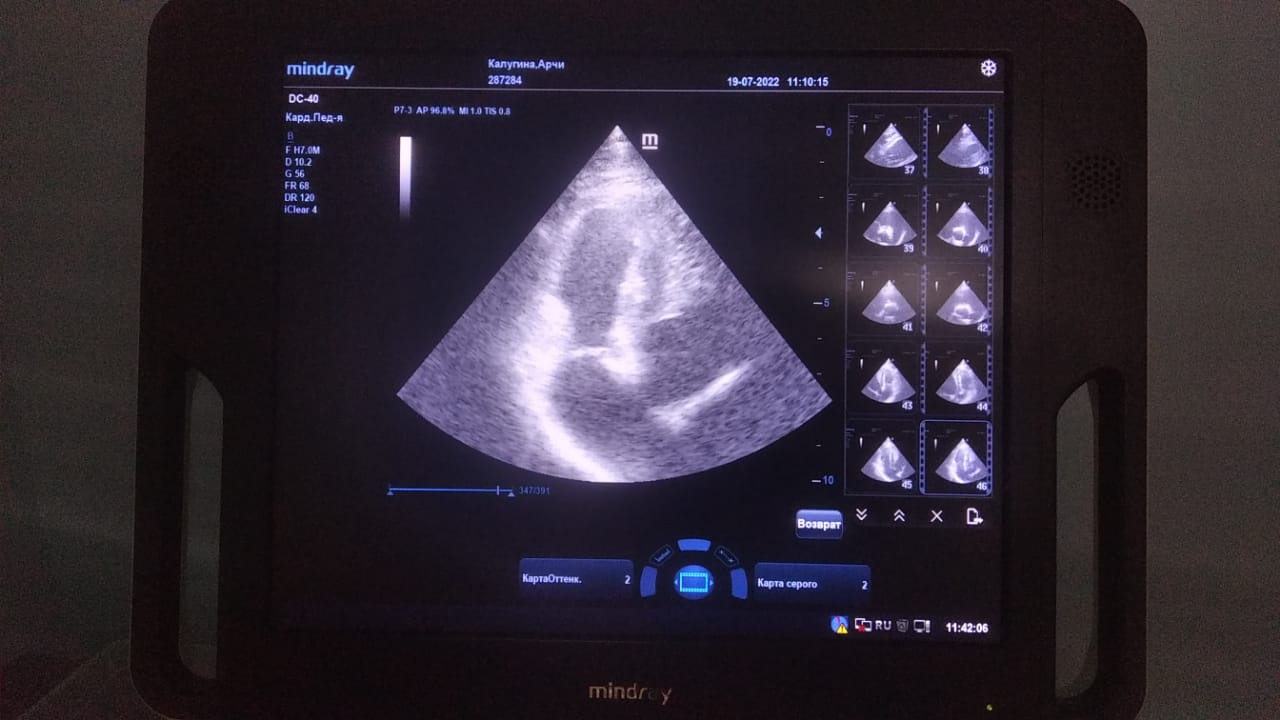

Анализы Арчи. Сердца и легких

Вложения

IMG-20220719-WA0100.jpg

IMG-20220719-WA0102.jpg

IMG-20220719-WA0104.jpg

IMG-20220719-WA0103.jpg

IMG-20220719-WA0105.jpg

Продолжение.